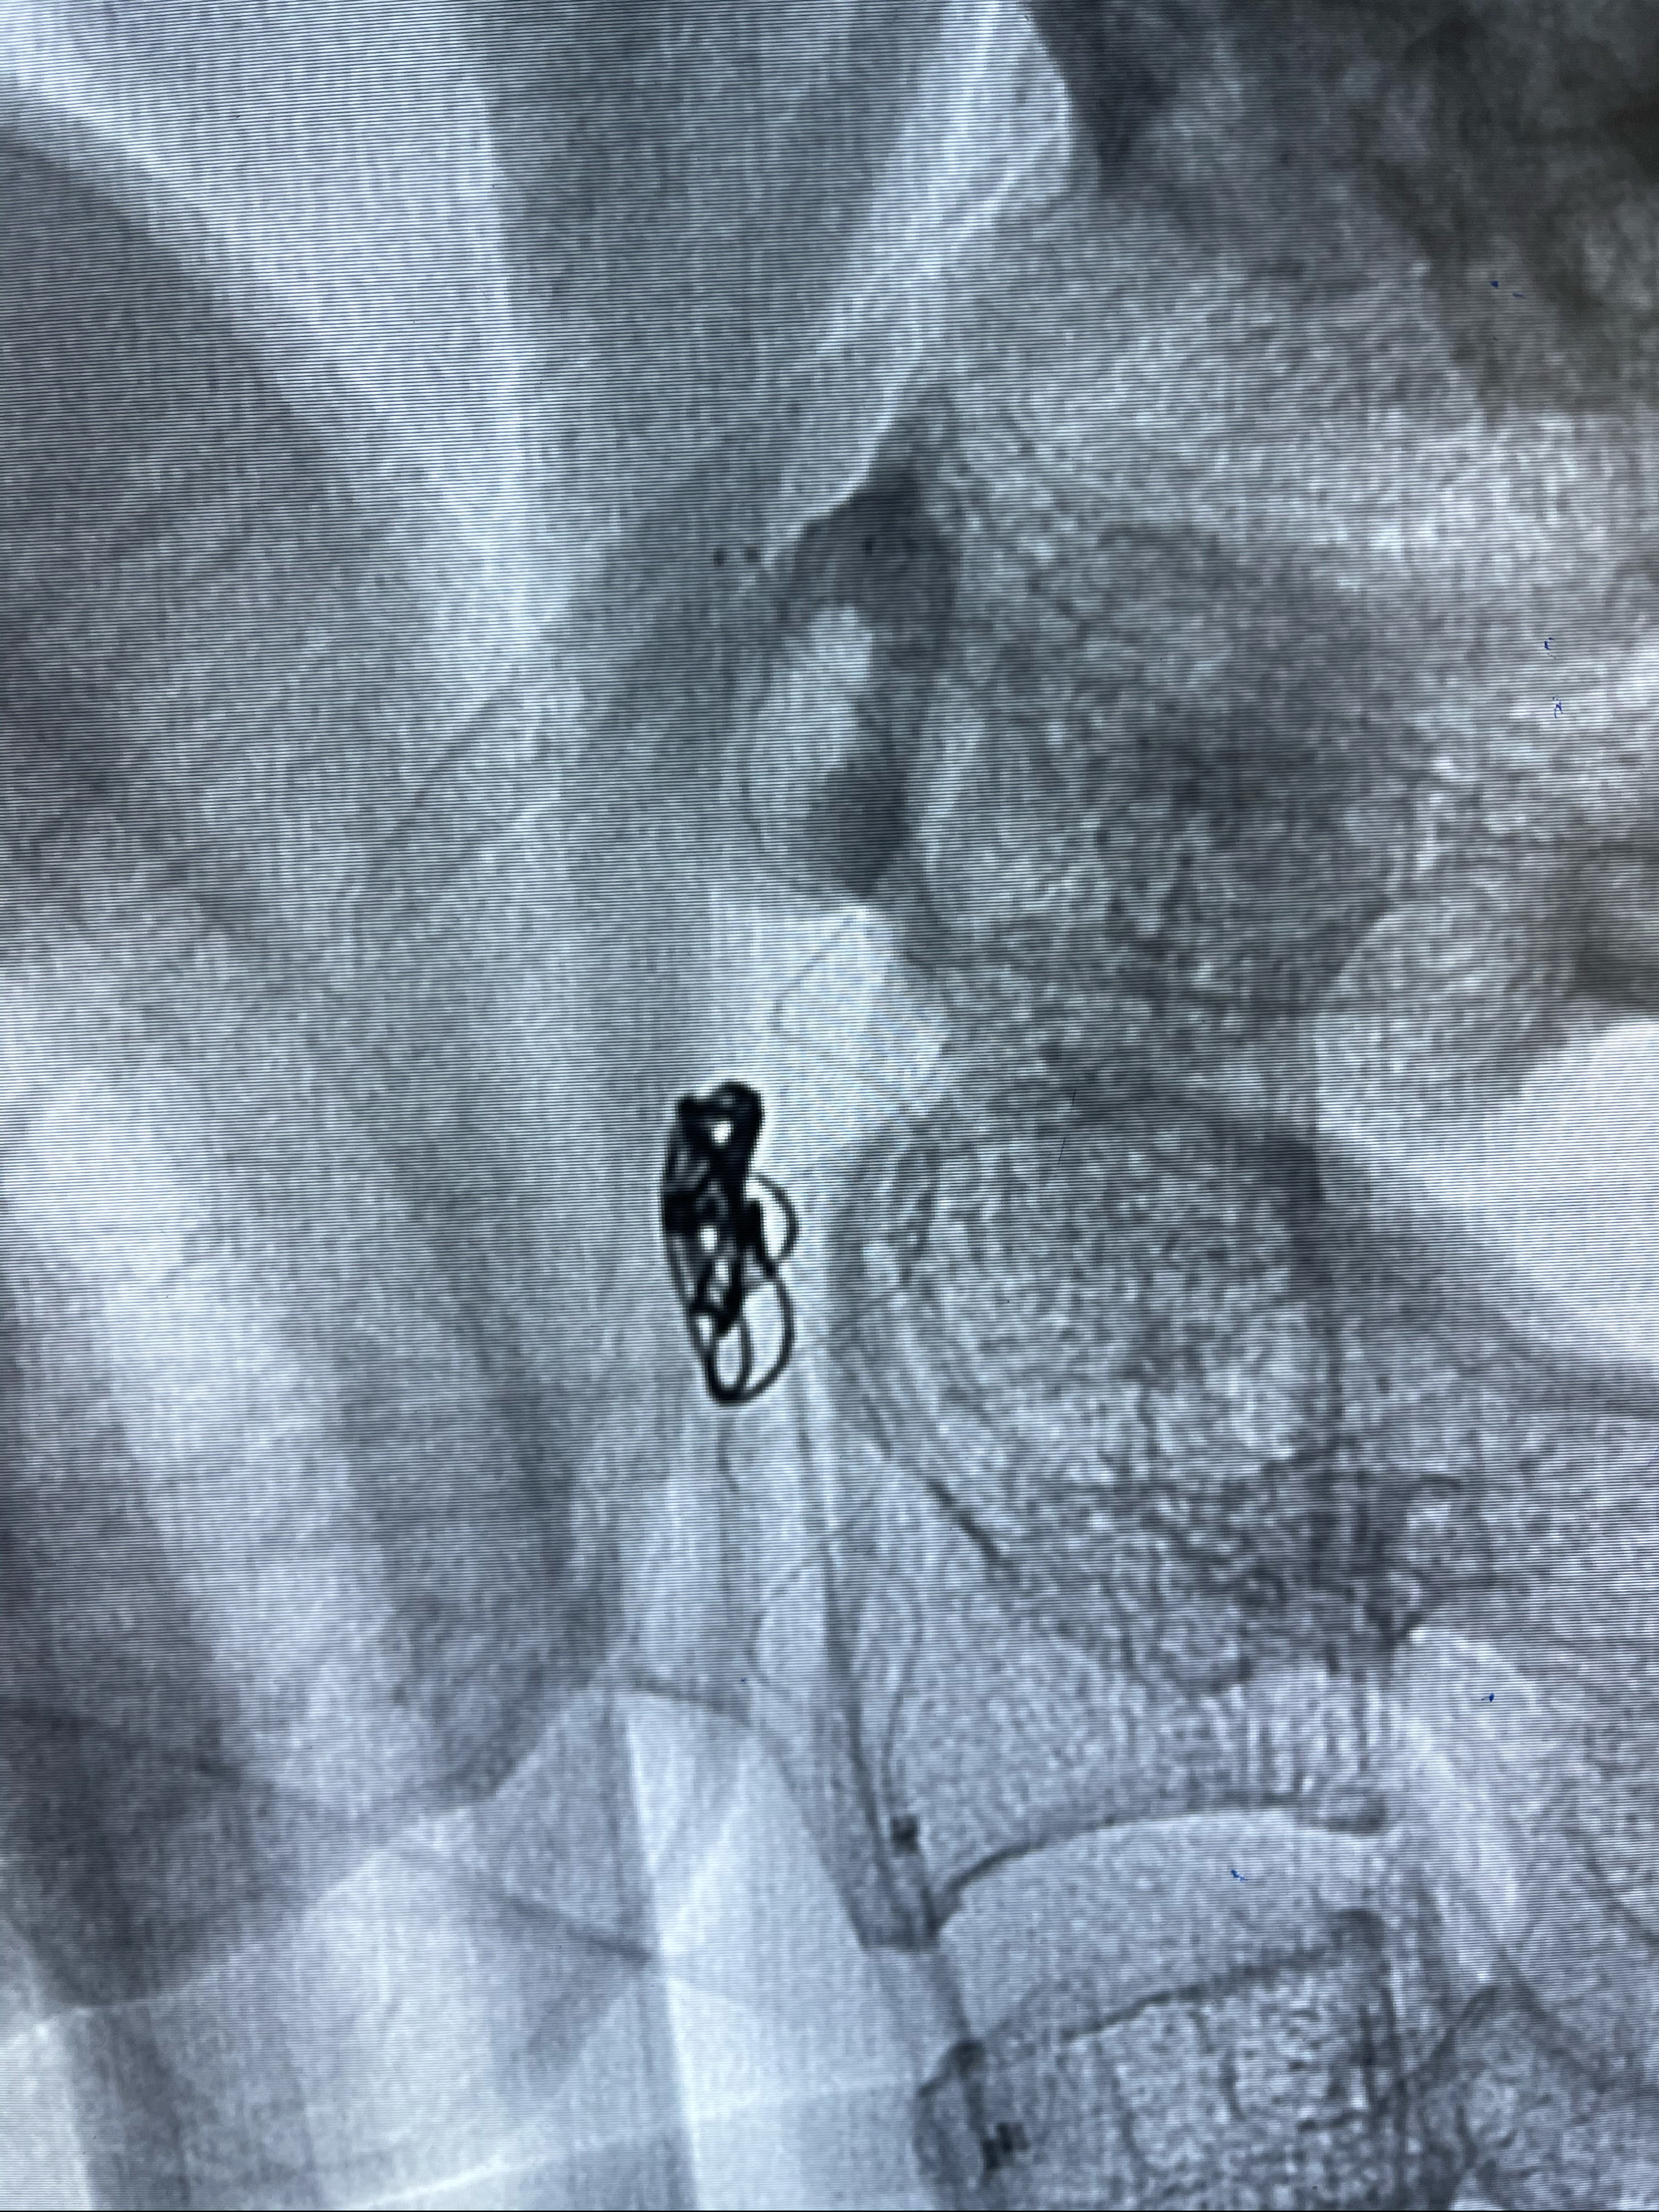

即刻造影

支架到位

支架释放,透视下